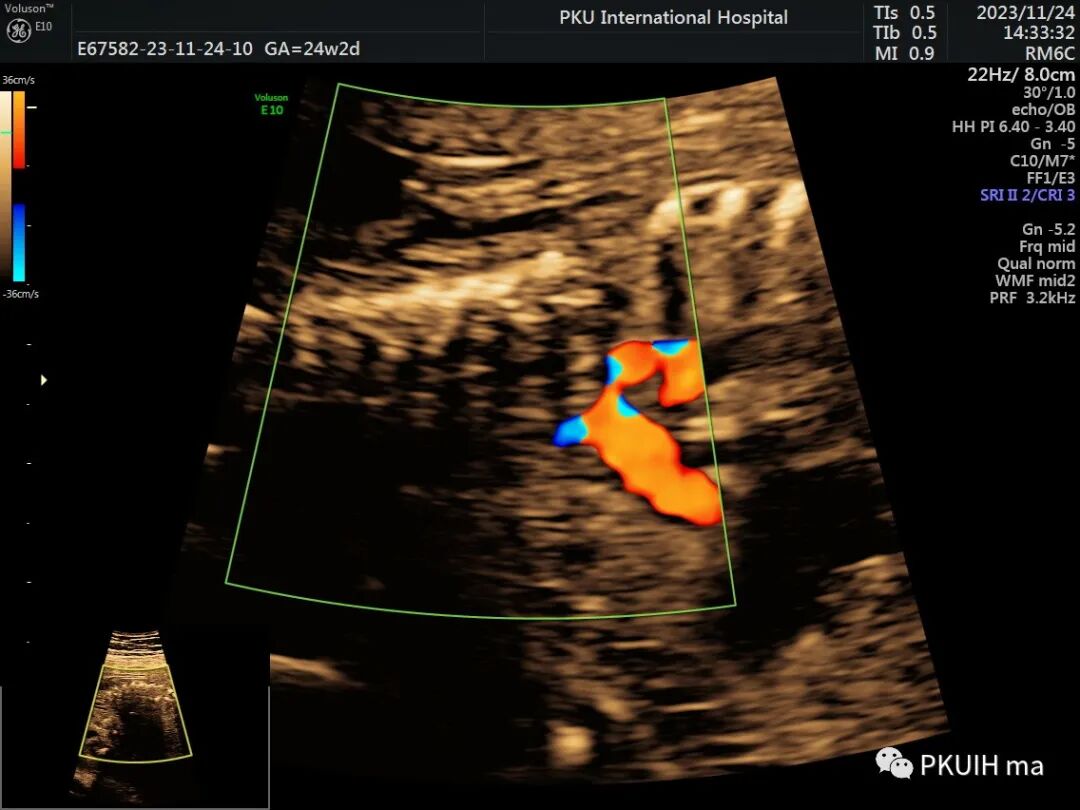

最后可借助于CDFI,CoA胎儿主动脉峡部出现持续性血流信号,当出现湍流时,CoA发生风险明显增加。严重的峡部可出现反向血流灌注。